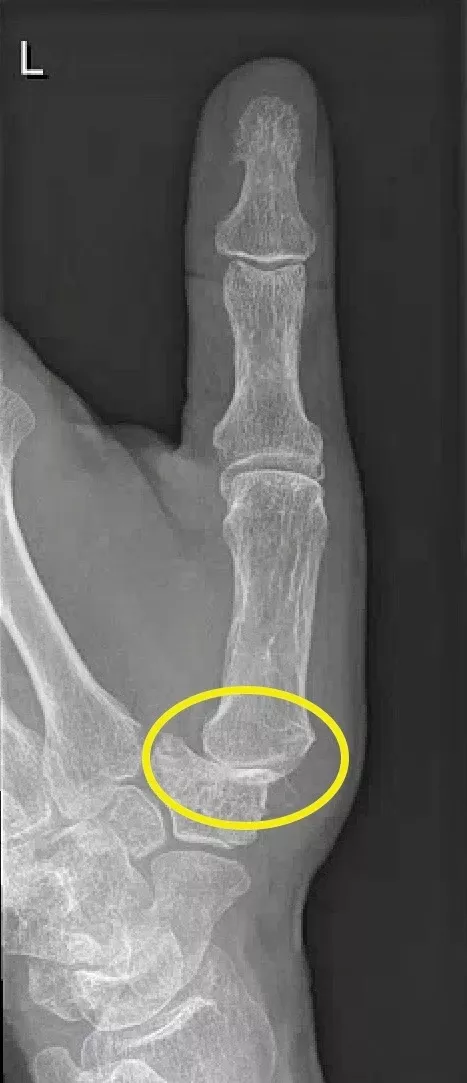

Skiduim

Wat is het?

Een skiduim is een scheur van het gewrichtsbandje (ulnair collateraal ligament) aan de binnenzijde van de duim, ter hoogte van het MCP-gewricht. Dit gebeurt meestal door een slag of val waarbij de duim naar buiten klapt. Het letsel kan:

- Gedeeltelijk of volledig gescheurd zijn

- Soms met een stukje bot me afscheuren (beenderige skiduim)

- Soms onder een pees terechtkomen, waardoor het niet spontaan kan genezen (Stener-letsel)